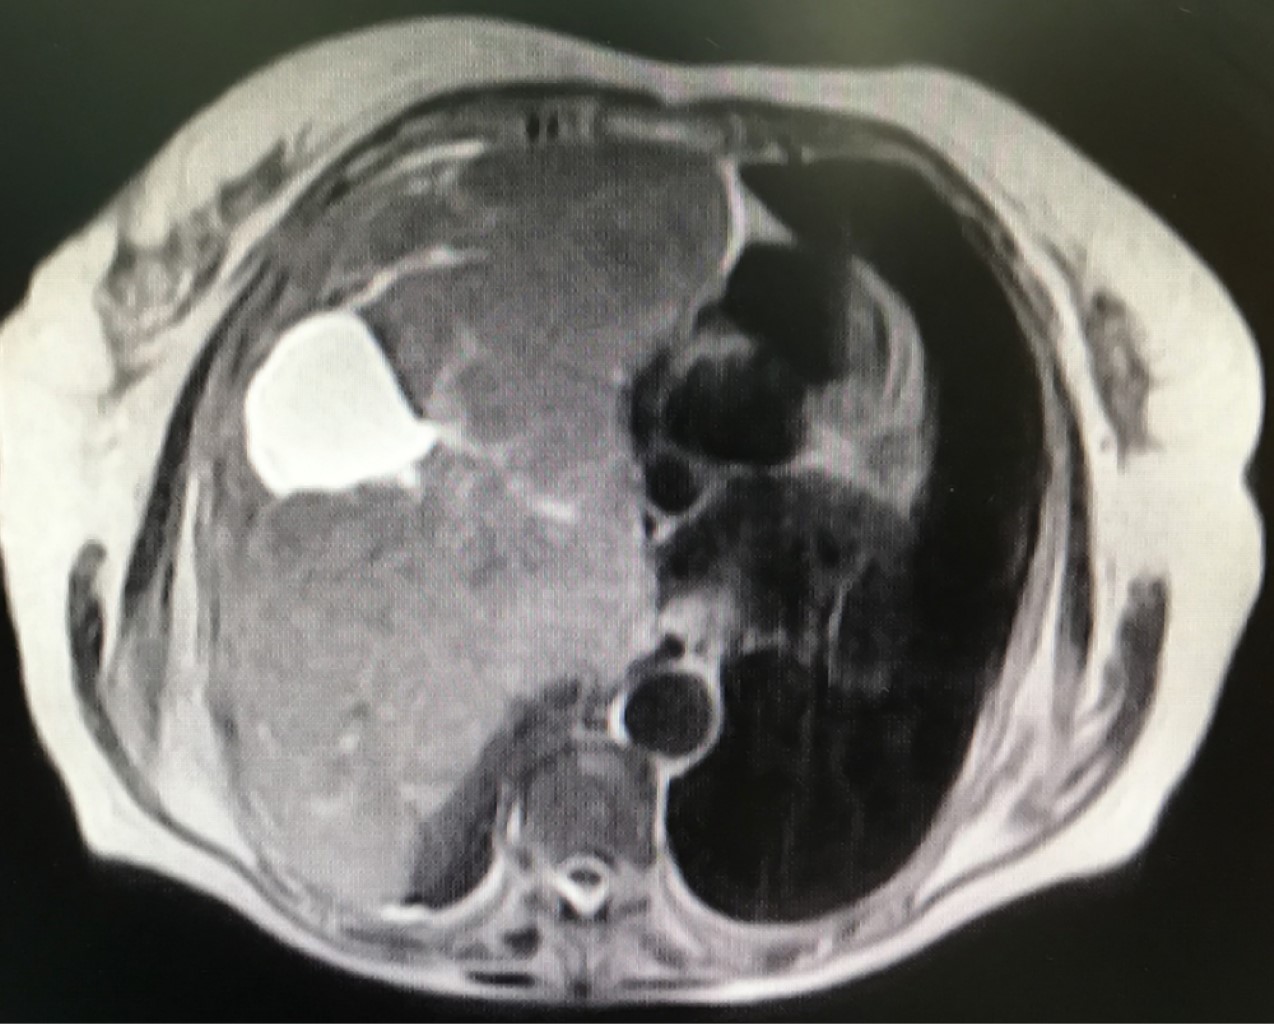

Se efectúa biopsia por punción. El informe de anatomía patológica es: tumor fusocelular, DC 34 negativo, ASMA positivo, S 100 negativo, NSE negativo, Ki67 2% que sugiere como diagnóstico leiomiosarcoma de bajo grado. Se solicita resonancia magnética para visualizar la presencia de infiltración, principalmente de grandes vasos (Figura 2), y estudios para enfermedad a distancia, sin encontrar imágenes compatibles (Figura 3) con metástasis. Se decide, junto con la paciente, familiares y Servicio de Oncología, la conducta quirúrgica para lograr extirpación completa o la mayor resección posible.

Figura 2